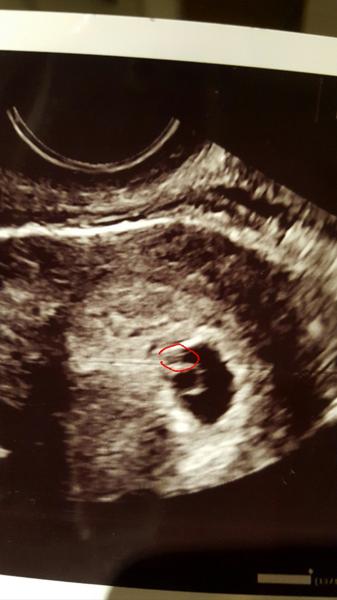

@jaannah Mne digitalny test uz dva tyzdne ukazuje 2-3 a mala som byt 6+2tt cize davno 3+. Vcera sono ukazalo, ze som max 5+4tt. Bojim sa hrozne, ze to moje vytuzene babenko vzdalo 😢 Mam kontrolu o dva tyzdne

@denidi Co sa ma stat sa stane..ale verim, ze moje babenko je silne a krasne porastie 🙂 Zvlastne je, ze neviem podla coho mi povedala, ze 5+4tt, pritom mi aj potvrdila, ze vidi maly plodik..len ze bol zle odmeratelny a musime pockat, teda sme ani srdiecko nehladali. Modlime sa s priatelom, a verime, ze to dobre dopadne!